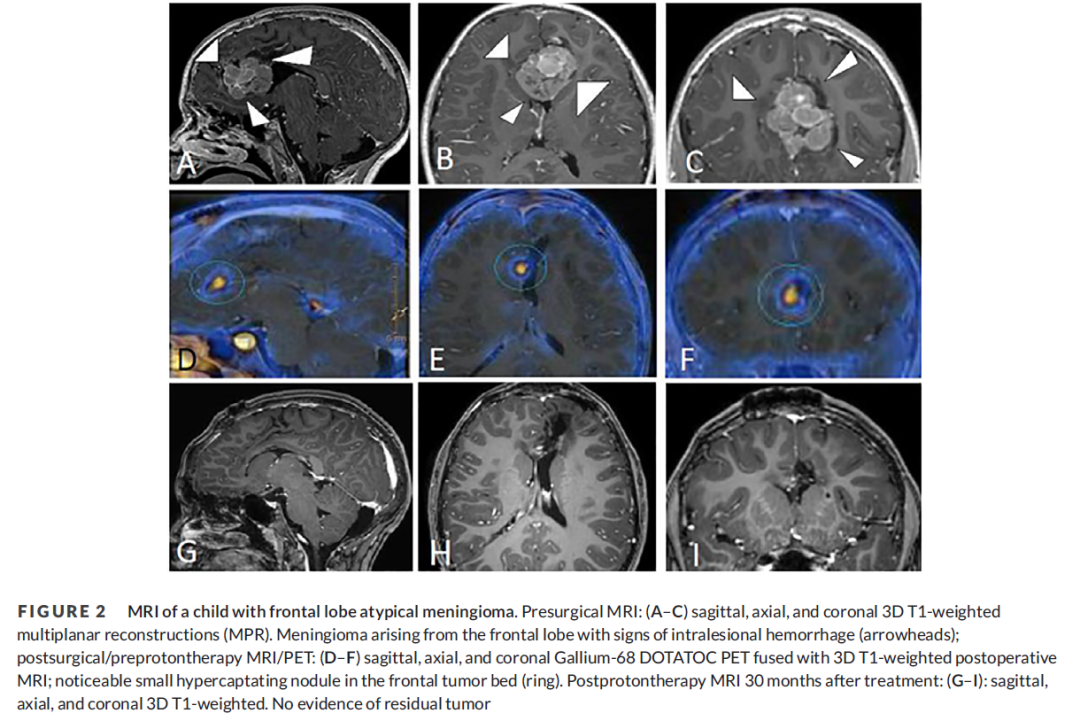

7岁男童,反复出现严重的头痛发作,伴有跌倒、震颤和尿失禁。MRI显示额叶肿块(50 70 50 mm),伴有病灶内出血迹象(图2AC)。患者接受了额旁正中入路手术。病理检查显示脑膜上皮细...